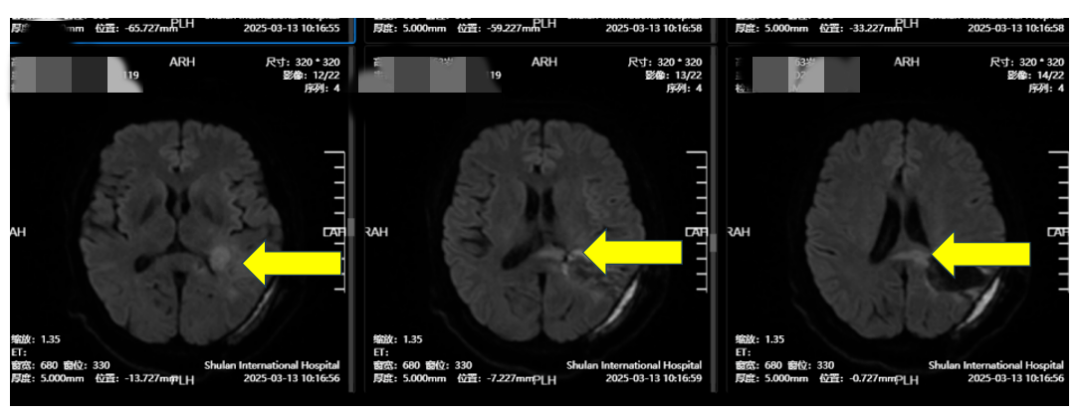

2月初,高女士因记忆力下降,思维迟缓和四肢无力就诊于山东某知名三甲大医院。进行PET-CT+颅脑MRT检查,提示“左顶叶、胼胝体占位性病变”。一场紧急手术切除了肿瘤,但术后病理报告却让其家属心中一沉——“胶质母细胞瘤”,这是恶性程度最高、侵袭性最强的脑肿瘤之一。

(图1:术前:左顶)

(图2:术前:左顶+胼胝体)